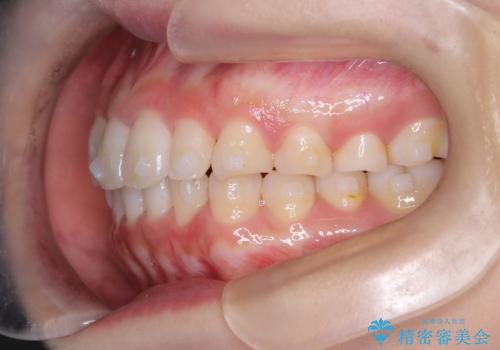

【インビザライン】八重歯が気になる

- 乳歯を抜歯してスペースを確保し八重歯の改善を行いました。

インビザラインをしっかり使用していただいたので、きれいな歯並びになりました。